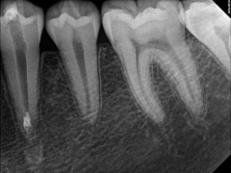

Every tooth has different numbers of roots and canal systems. With the help of magnification and high tech equipment, Dr. Jung can locate and treat the canals including MB2 on upper molars and MM on lower molars.